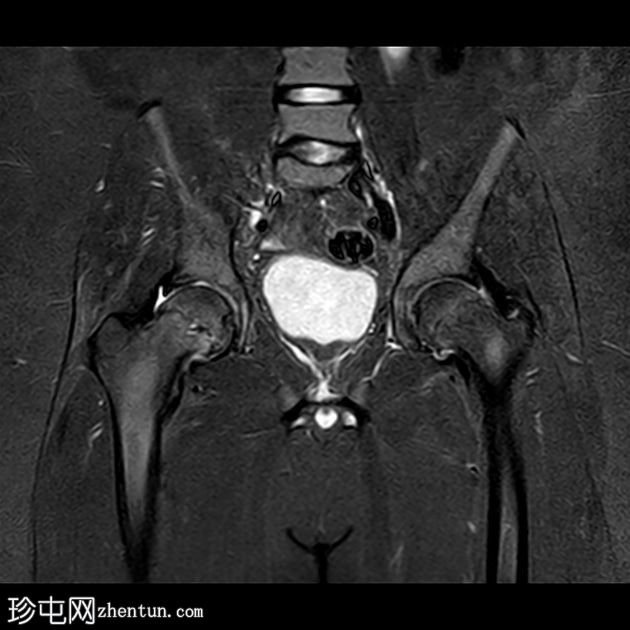

MRI

4.jpg

冠状位片

T1加权像

双侧股骨近端骨骺皮质不规则,轻度增宽,伴股骨骨骺及近端干骺端骨髓水肿。

双侧股骨骨骺轻度后内侧移位。

双侧轻度髋关节积液。